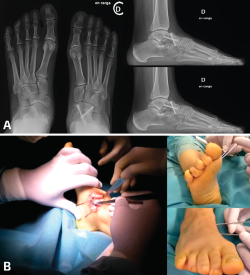

- Demasiado valgo: algunas dobles/triples artrodesis tarsianas pueden acabar fijadas con un excesivo valgo. Las consecuencias clínicas serían las opuestas al escenario descrito anteriormente y los signos radiológicos serían también los contrarios. Lo que no varía es el planteamiento de corrección para llegar al CORA de la deformidad y poder realizar osteotomías correctoras. La modificación de la alineación suele conllevar también una mejoría importante en el dolor del tobillo (Figura 4).

Figura 4. Paciente con consolidación viciosa de una doble artrodesis tarsiana que muestra excesivo valgo y un tobillo con una artropatía asimétrica y muy doloroso. A: el estudio radiológico muestra la deformidad en valgo y la transmisión de ese valgo a la tibiotalar; B: en las imágenes de radioscopia intraoperatoria se aprecia la realización de una osteotomía varizante de calcáneo y de una osteotomía de cierre talonavicular con una cuña de base medial y plantar; C: radiografías de ambos pies en carga en proyección dorsoplantar que muestran las diferencias en la alineación al año de la cirugía; D: misma situación en proyección lateral; E: radiografías de ambos tobillos en carga en proyección anteroposterior que muestran las diferencias en la asimetría al año de la cirugía. La paciente se encontraba asintomática de su dolor tibiotalar.